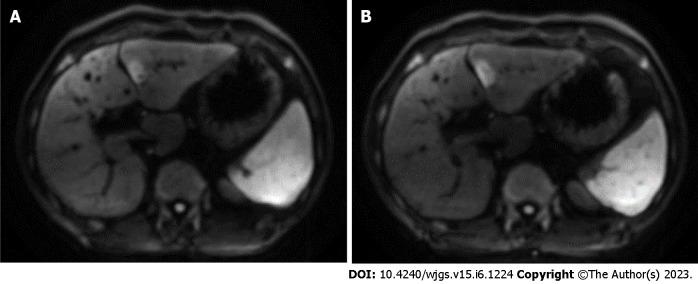

We present two cases of ICC in patients with PSC associated with UC. In the first case, a tumor was found by magnetic resonance imaging (MRI) in the liver of a patient with PSC and UC who presented to our hospital with right-sided rib pain. The second patient was asymptomatic, but we unexpectedly detected two liver tumors in an MRI performed to evaluate bile duct stenosis associated with PSC. ICC was strongly suspected by computed tomography and MRI in both cases, and surgery was performed, but unfortunately, the first patient died of ICC recurrence 16 mo postoperatively, and the second patient died of liver failure 14 mo postoperatively.

我们报告了2例与UC相关的PSC患者发生ICC的病例。第一例,一名患有PSC和UC的患者因右侧肋骨疼痛前来我院就诊,通过磁共振成像(MRI)在其肝脏中发现了一个肿瘤。第二例患者无症状,但在为评估与PSC相关的胆管狭窄而进行的MRI检查中,我们意外地在其肝脏中检测到两个肿瘤。两例病例通过计算机断层扫描和MRI均高度怀疑为ICC,并进行了手术,但不幸的是,第一例患者术后16个月死于ICC复发,第二例患者术后14个月死于肝功能衰竭。